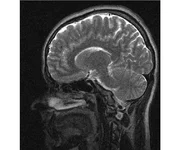

делал в обласной на siemense.В заключении выданом мне через 15мин.после мрт (легкая дегидрация)

Меня смутил факт выдачи заключения через 10мин(наверно они у них зарание напечатаные)я не медик.достаточно мимолётного взгляда на снимки?А вы видете на них гидроцефалию? Я лиш спросил куда идти с результатами томографии?и не хотел никого роздражать.

Я попросил взглянуть на снимки и сказать видна.ли на них гидроцефалия?или куда обратится за консультацией по этому вопросу?В мрт снимках наверно розбирается любой нервопатолог(я так предположил)

Я уже говорил, что независимо от того, есть на МРТ гидроцефалия или нет, лечиться тебе нужно только в том случае, если есть какие-либо проявления болезни, иначе на все эти анализы можешь забить... Но давай все-таки разберемся с томограммой.

Итак, с самого начала томограмма обозначала срез какого-либо органа на определенной глубине, позволяла заглянуть вовнутрь. При компьютерной томографии аппарат делает десятки срезов головного мозга в разных направлениях и из этого множества срезов он моделирует полноценное объемное изображение мозга в натуральную величину. Обрати внимание, компьютер работает не с этими миниатюрными изображениями, а с трехмерной моделью в масштабе 1:1. Эту модель вдоль и поперек анализирует суперсовременный компьютер, выполняющий миллионы операций в секунду. Только ***** может пытаться перепроверить компьютер, ведь человеку не хватит всей жизни чтобы проанализировать то, что компьютер с тобой сделал за 10 минут. Я хочу, чтобы ты это понял!

Ты разместл здесь несколько миниатюр и хочешь, чтобы врач по ним создал полноценное объемное изображение в натуральную величину, а потом осмотрел его со всех сторон и дал заключение? Но ведь это невозможно. Это просто насмешка над врачом, это издевательство над здравым смыслом. Принеси Букеру уменьшенный в 50 раз снимок зуба и спроси у него, в каком состоянии там корневые каналы. Или давай я дам тебе скрин со спутниковой карты города и попрошу тебя описать, какого цвета и какой модели запечатленная со спутника машина, какой у нее гос.номер, сколько в ней пассажиров, сколько из них мужчин и сколько женщин...

Надеюсь, ты понимаешь, что это невозможно. И воссоздать по приведенным тобой аватарам полную картину мозга тоже невозможно. Пойми, если уж называть вещи своими именами, то ты запостил полнейшую ***ню! Ты не хотел никого обидеть, ты ведь сам не ведал, что творил. Ты продемонстрировал полнейшую медицинскую безграмотность и полное невежество, но претензий к тебе нет. Ты ведь не один такой. Ты пожелал того, что сделать невозможно, и тут же у тебя нашлась сочувствующая, некая П., которую, по большому счету, надо бы послать в П., коль уж она считает, что врач должен тут сделать немедленно и бесплатно то, что делает немецкий компьютерный томограф ценой в миллионы долларов.